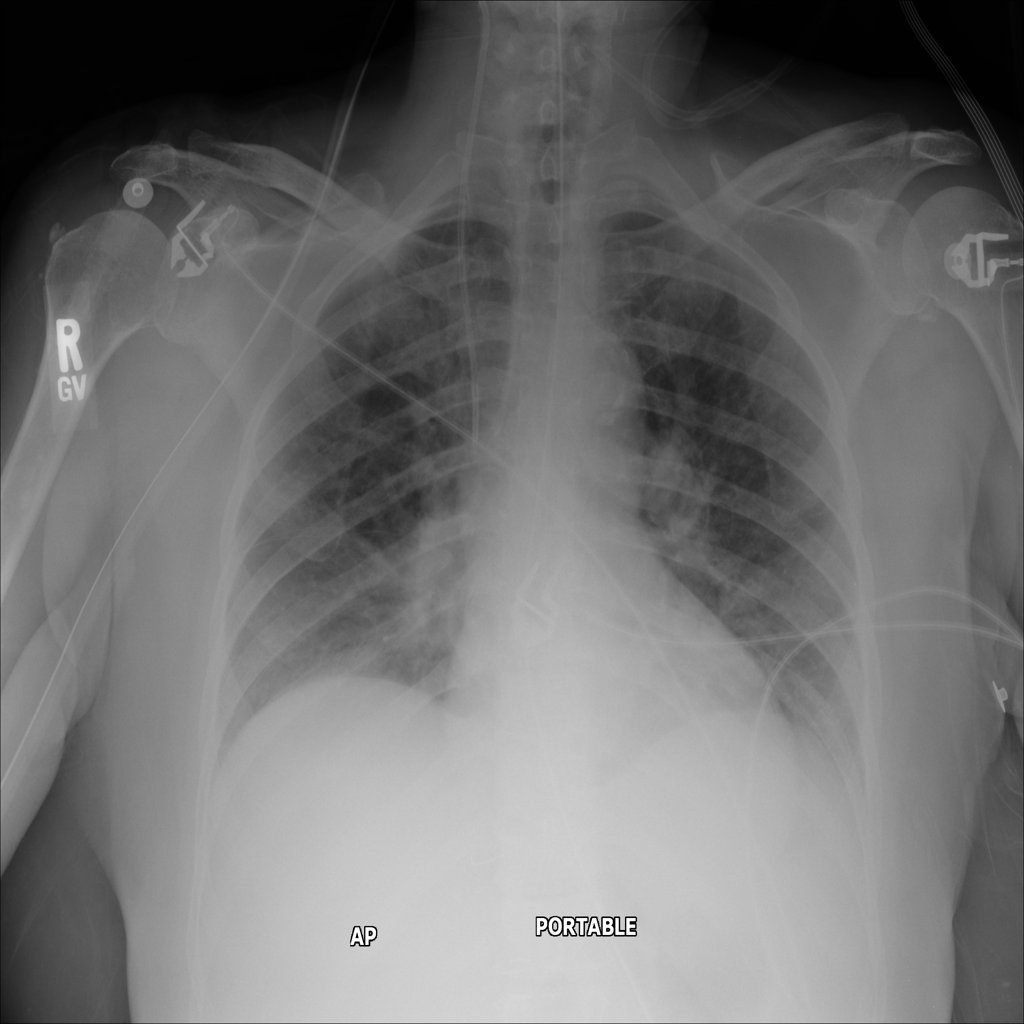

PAT-8B05 · IMG-002Atelectasis

PAT-8B05 · IMG-002

AP

PAT-8B05 · IMG-003Atelectasis

PAT-8B05 · IMG-003

PA